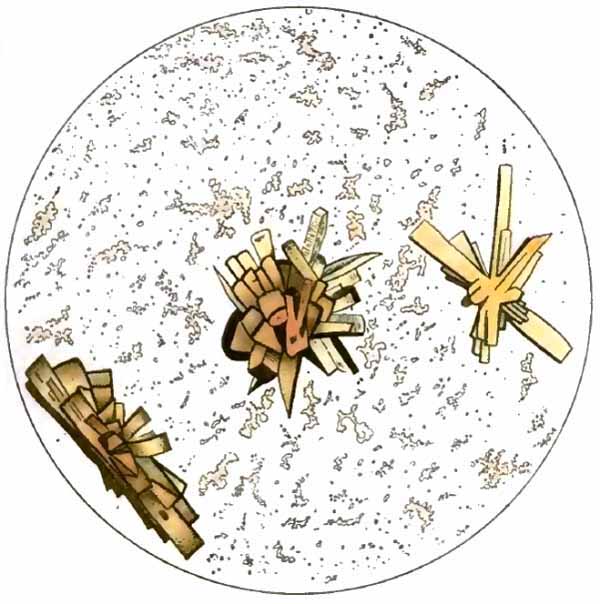

| FIG. 8.—Sputum from a case of actinomycosis; stained (Jakob). |

5. Actinomyces Bovis (Ray-fungus).—In the sputum of pulmonary actinomycosis and in the pus from actinomycotic lesions elsewhere small, yellowish, "sulphur" granules can be detected with the unaided eye. The fungus can be seen by crushing one of these granules between slide and cover, and examining with a low power. It consists of a network of threads having a more or less radial arrangement, those at the periphery presenting club-shaped extremities (Fig. 8). This organism, also called Streptothrix actinomyces, apparently stands midway between the bacteria and the molds. It stains by Gram's method.

[p. 32] Actinomycosis of the lung is rare. The clinical picture is that of tuberculosis.